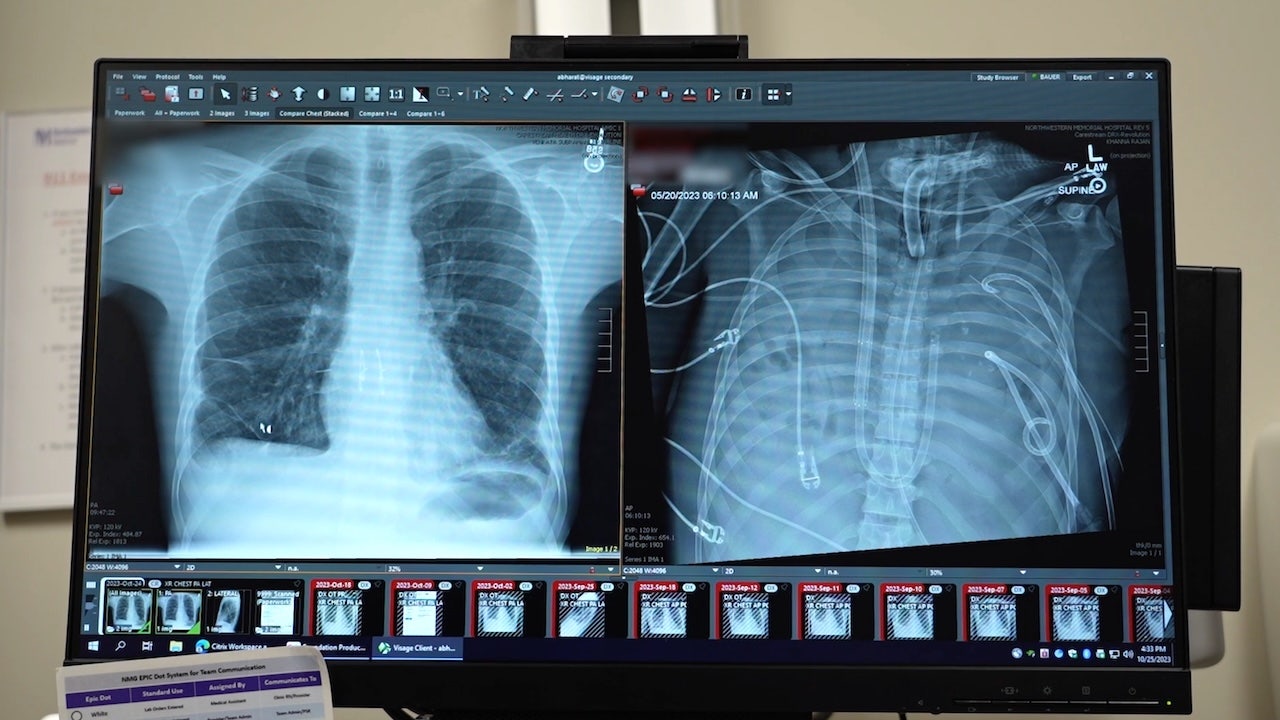

Surgeons at Northwestern Medicine in Chicago were able to keep a critically ill patient alive for 48 hours after removing both of his lungs, the hospital reported last week.

The patient, a 33-year-old Missouri resident whose name was not shared, was originally flown to Northwestern Memorial Hospital with lung failure linked to a flu infection in spring 2023.

“He had developed an infection of his lungs that just could not be treated with any antibiotics because it was resistant to everything,” said Ankit Bharat, M.D., chief of thoracic surgery and executive director of the Northwestern Medicine Canning Thoracic Institute. “That infection caused his lungs to liquify and then continued to progress to the rest of his body.”

In a case study, which was published last week in the Cell Press journal Med, experts revealed a “molecular analysis” of the removed lungs, showing extensive scarring and damage. This supports the idea that in some severe cases of acute respiratory distress syndrome, transplantation may be the only viable option.